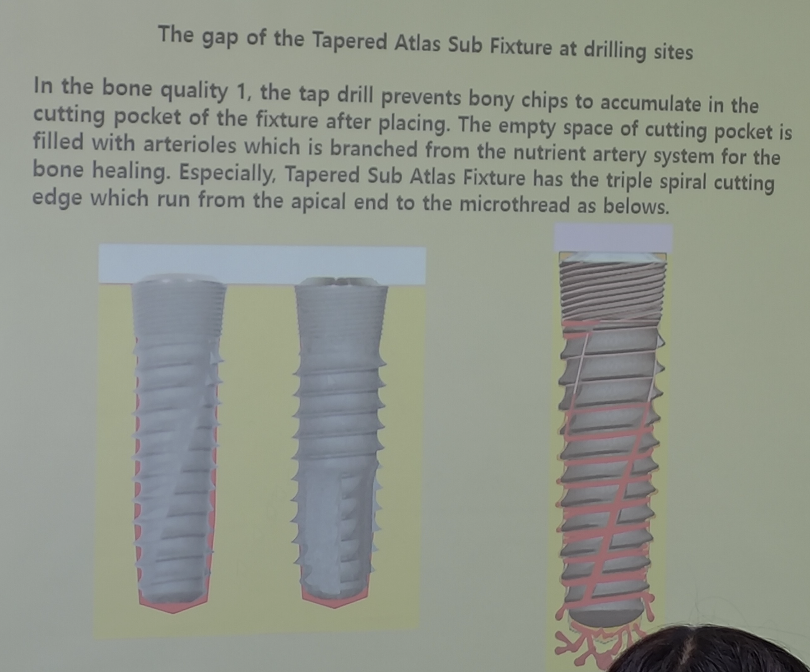

- Cortical bone Level: 細螺紋,卡緊

- Bunddle bone Level: 粗螺紋,長細胞

- implant 植入不能晃,但要有血液上來的空間

- Drill 比 implant 深

- Drill 比 implant 深